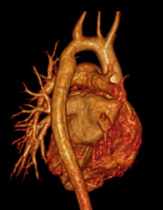

Description: Congenital heart diseases are heart problems that children are born with. These diseases range from simple to complex and many require surgery or other procedures.

Why MRI: Heart MRI is used to capture images in all types of congenital heart disease and at all ages. It can be used to help determine if and what type of surgery might be needed. It can also be used after surgery for routine follow up and check if there are any complications.

Heart MRI captures images of the heart and blood vessels to help see exactly the location and size of the structures. Sometimes 3D models are made to help see everything. Heart MRI can also measure flow in blood vessels and measure how well the heart muscle is pumping.

Images: ASD, 3D aorta, Flow in single ventricle